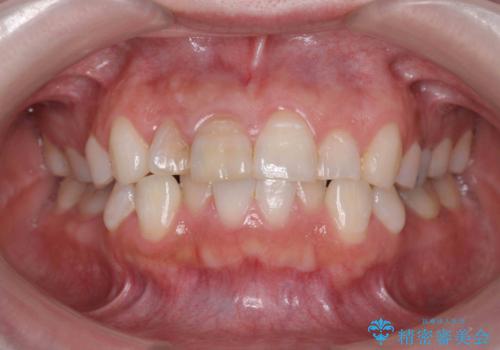

前歯の変色 セラミッククラウンによる審美性の回復

- 前歯が徐々に神経の治療を行ってから変色し、審美性の回復を求めて来院されました。

根尖に病変は見られず、根管治療は行わずに仮歯・ジルコニアクラウンを作製、装着することで審美性を回復しました。

神経の治療を行った歯は、徐々に変色し審美障害をきたすことはから当院ではセラミッククラウンの装着をお勧めしております。